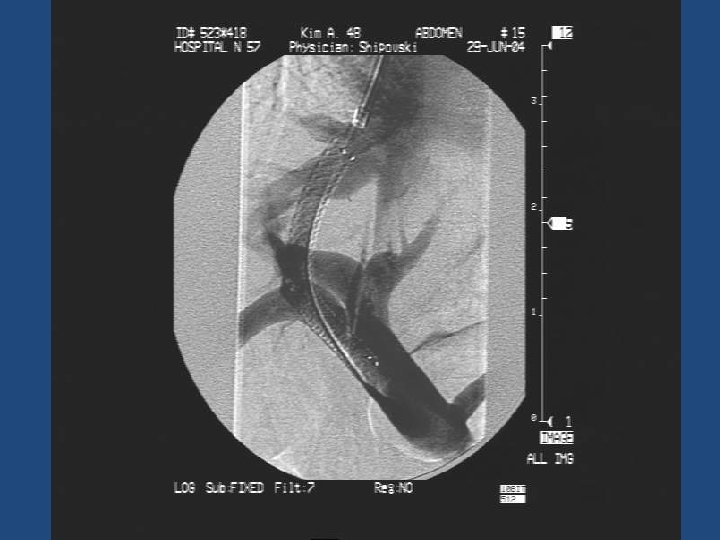

Результаты TIPS • • • Длительность процедуры 1 час до 3, 5 часов Повторные кровотечения – 10% Стеноз стента в течение двух лет – 20% Печеночная энцефалопатия Летальность 20% Максимальный срок наблюдения = 5 лет

Методика дистанционного обследования после TIPS • Клинический осмотр и лабораторные анализы • ЭГДС • Ультразвуковое дуплексное исследование портального кровотока • Ангиография ?